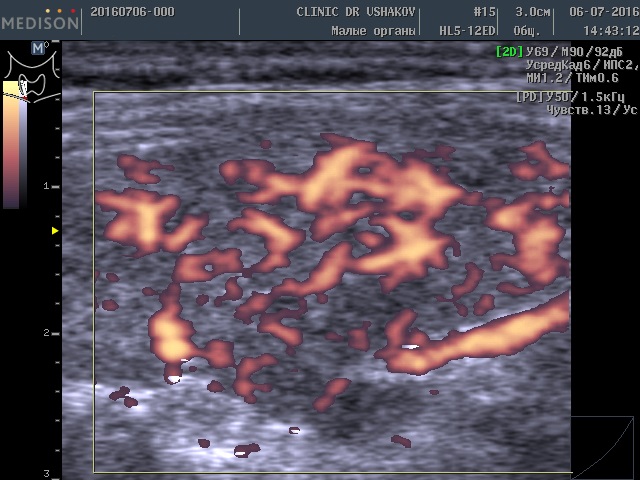

Такое более интенсивное усвоение организмом щитовидных гормонов (Т4 и Т3) вынуждает сильнее заставлять щитовидную железу производить эти гормоны. Избыточная стимуляция происходит с помощью гормона ТТГ (из гипофиза) и шейной части периферической нервной системы. Нервные клетки из нервных центров направляют свои увеличенные стимулы к ткани щитовидной железы, заставляя интенсивнее производить гормоны, и одновременно с такой же силой активизируют кровоток внутри железы, стремясь при этом доставить к ткани железы больше продуктов (для питания и образования гормонов). Вот почему у этой пациентки при УЗИ в нашей Клинике мы выявили умеренное усиление кровотока (рис. 1 и 2). Это заметно на снимках, где в специальном режиме для оценки сосудов (ЭДК) определяется увеличенное количество красных элементов (преимущественно увеличенного размера). Такая картина УЗИ не редко встречается при малом или умеренном гипертиреозе (с тиреотоксикозом), который врачи называют «повышением функции щитовидной железы».

Рисунки 1 и 2. Пациентка В., 32 г. левая и правая доли щитовидной железы в режиме ЭДК. Кровоток умеренно усилен в обеих долях (обозначен красным цветом).